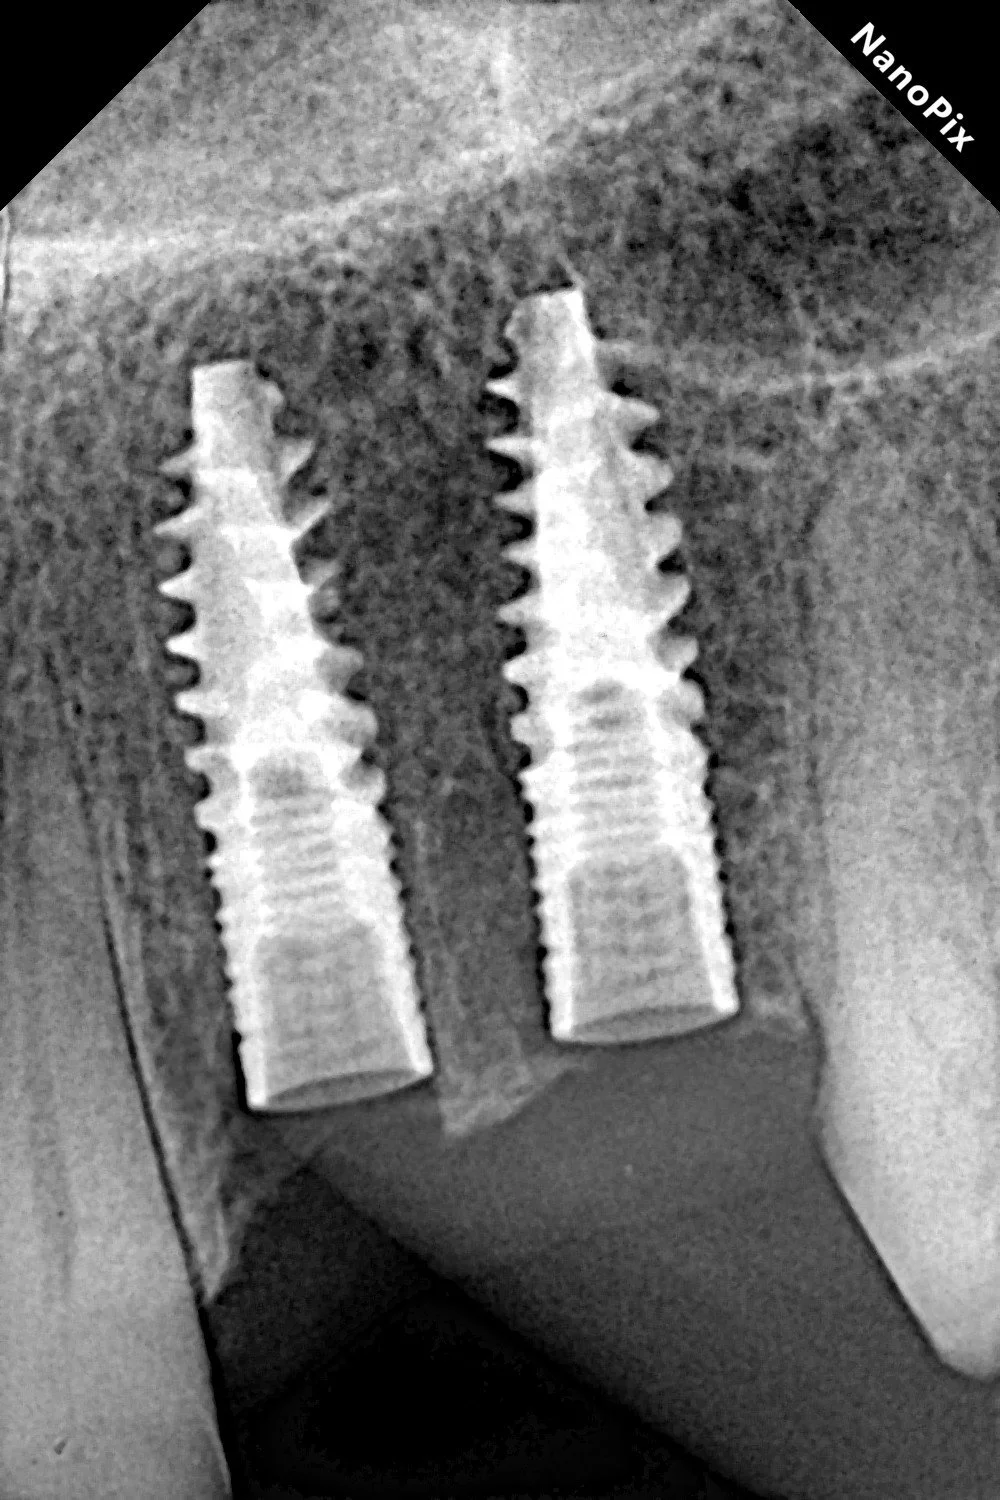

This phase is the easiest part of the whole procedure, as it is direct application of the previous one. The entire phase took only less than 30 minutes. Post-operative X-rays confirmed perfect implant positioning and parallelism.